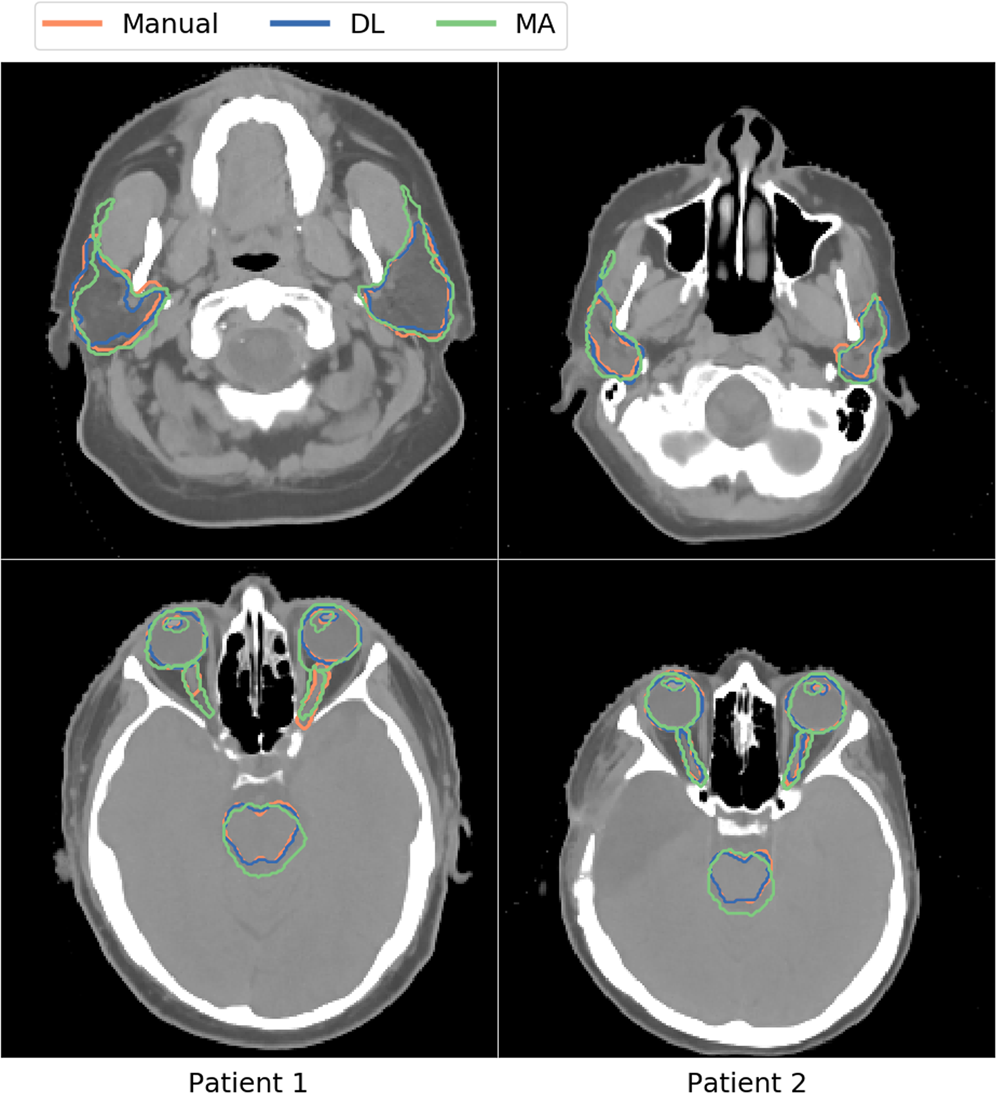

Figure 6

Comparison of the manual (orange), deep-learning (DL; blue), and multi-atlas (MA; green) based image segmentation methods for all organs-at-risk for two patients.